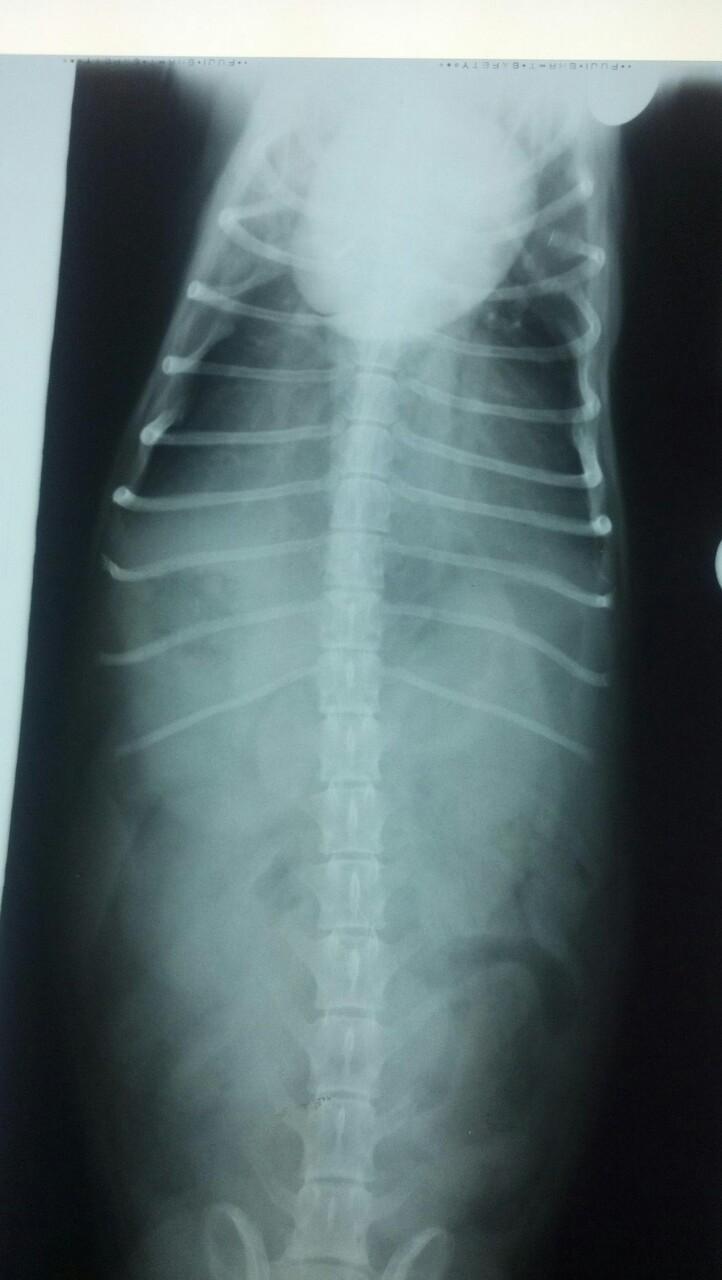

The patient is a 13 year old spayed female Dachshund dog which was presented for four days of anorexia and vomiting. She was given Cerenia, which helped, but still had ileus. Dog has vomited carpet material in past. Spec cPL was normal. Radiographs revealed dilated intestine, which appeared to be colon and cecum.